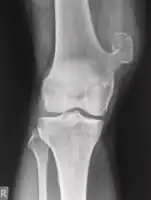

Medical imaging usually shows a well-defined wide-based bony growth on the surface of bone.[5] It can be pedunculated and irregular, giving it a "bizarre" appearance, and is not connected to underlying bone.[2]

X-ray left foot: Bizarre parosteal osteochondromatous proliferation in 2nd toe